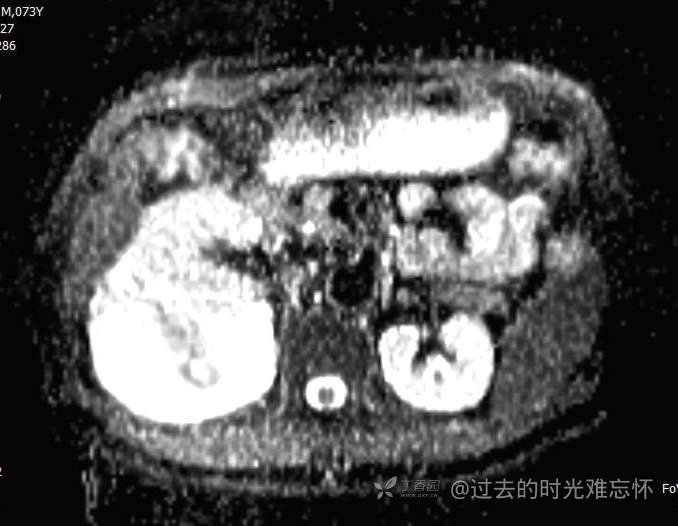

患者性别:男

患者年龄:73岁

主诉:咳嗽1月余。曾有血尿一次。后背部酸痛不适1-2年左右,无明显消瘦。

辅助检查:CT MRI

临床诊断:占位

治疗经过:手术